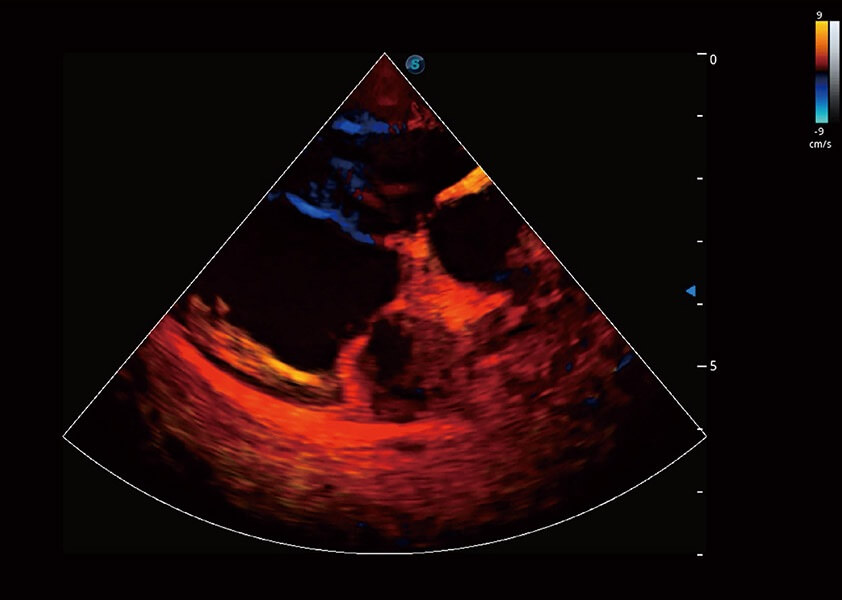

ProPet 60 作为一款高端台式动物超声设备,为动物医生的日常诊断提供了一系列贴合动物临床需求、解决临床实际问题的高级成像功能。凭借全系列高清探头,满足医生对腹部、心脏、生殖、浅表、肌骨等成像的所有需求,切实帮助您提升检查效率,提高诊断信心。

兽用彩色多普勒超声诊断系统

动物是人类最亲密的朋友和最值得信赖的伙伴。DB中国旗舰官方网站也一直致力于探索动物专用的超声影像解决方案。 全新推出的ProPet系列,是DB中国旗舰官方网站在动物超声影像智能化、专业化、精准化的一次跨越式革新。动物不能用言语来表述自己的不适,通过超声影像,ProPet系列搭建了动物医生与不同物种沟通的“桥梁”,为动物医生注入了“治愈之力”。